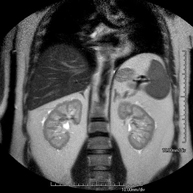

- RM Riñones

Prueba diagnóstica no invasiva que consiste en la obtención de imágenes de alta definición anatómica de ambos riñones mediante el empleo de un campo electromagnético y ondas de radio (con un emisor y un receptor). No utiliza radiación ionizante. Se realiza para estudiar cualquier lesión localizada en ambos riñones. Normalmente se requiere el uso de contraste paramagnético (Gadolinio) para caracterizar las lesiones.